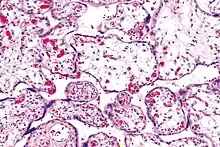

| Micrograph of villous immaturity. H&E stain. | |

Immature chorionic villi are larger and have more central blood vessels; thus, the diffusion distance for gas and nutrient exchange is larger and, therefore, placental function is impaired.